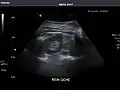

- Right kidney

Kidneys: Right and left kidneys measure 11.5 cm and 12 cm in length respectively. No hydronephrosis. Small left lower pole kidney cyst.